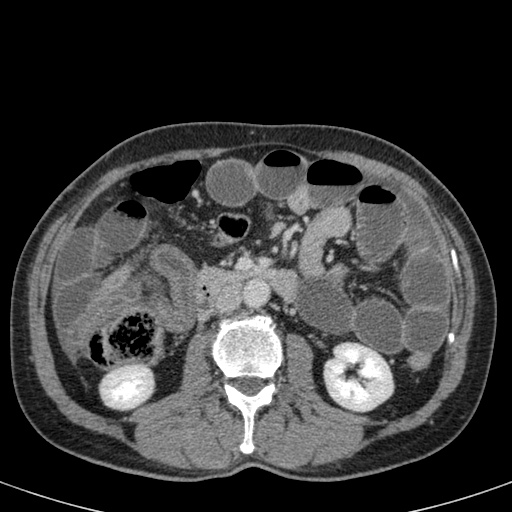

Đây là một bệnh nhân bị tắc ruột non.

Cuộn qua các hình ảnh.

Bạn có thể tìm thấy quai kín và nguyên nhân gây ra nó không?

Khi tiếp nhận bệnh nhân tại phòng cấp cứu với biểu hiện nghi ngờ tắc ruột non (SBO), điều quan trọng nhất chúng ta cần làm, ngoài việc chẩn đoán xác định, là xác định sự hiện diện hay vắng mặt của tình trạng thắt nghẹt.

CT là phương pháp chẩn đoán hình ảnh được lựa chọn trong đánh giá bệnh nhân nghi ngờ tắc ruột non.

Hình ảnh CT của tắc ruột non dạng quai kín phụ thuộc vào hai yếu tố:

- chiều dài đoạn ruột tạo thành quai kín

- hướng của quai ruột so với mặt phẳng tạo ảnh

Nếu quai kín ngắn và nằm trong mặt phẳng tạo ảnh, chúng ta sẽ thấy quai ruột hình chữ U hoặc chữ C.